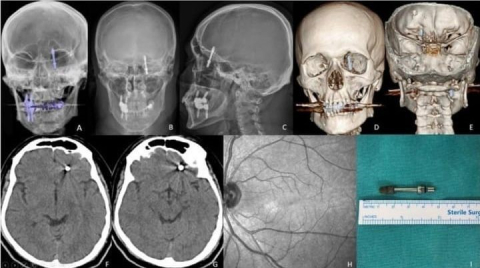

İddiaya göre, doktorun hatalı müdahalesi sonucu implant vidası çene kemiğini delip kafatasına saplandı. Ölümle burun buruna gelen talihsiz adam, saatler süren ameliyatla hayata tutundu. Ancak aradan geçen 2 yıla rağmen ne adalet yerini buldu, ne de sorumlular cezalandırıldı. Hatalı bulunan diş hekimine ise sadece 10 muayene ücreti ceza verildi.

Nilüfer ilçesinde özel bir diş kliniğinde muayene olan Yılmaz’a, dişlerinin sallandığı gerekçesiyle implant tedavisi önerildi. Ancak iddiaya göre, doktor A.D.’nin hatalı müdahalesi sonucu implant vidası çene kemiğini delip kafatasına saplandı.

Baygınlık geçiren Yılmaz, kliniğin kendi aracıyla hastaneye kaldırıldı. Tomografi çekiminde vidanın beynine kadar ilerlediği ortaya çıktı. Acil ameliyata alınan talihsiz adam, saatler süren operasyonla ölümden döndü.